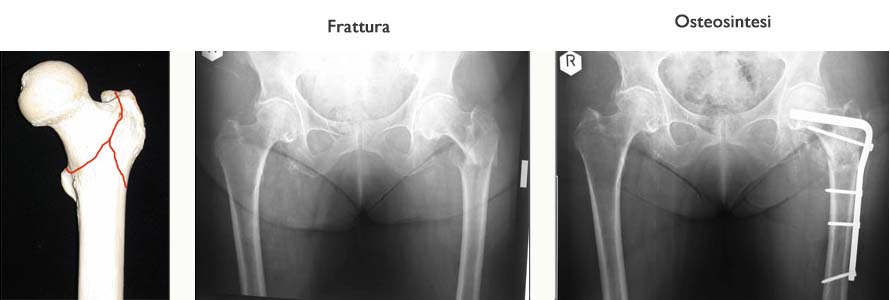

Le fratture del bacino sono eccezionali nel bambino, relativamente frequenti nell’anziano che soffre di osteoporosi. Nell’adulto giovane si tratta di fratture dopo un trauma molto violento e la gravità di queste lesioni dipende dallo spostamento dei frammenti e quindi dal coinvolgimento delle parti molli (vasi, arterie, vene, nervi).

Le fratture complesse del bacino sono traumi che mettono l’individuo in pericolo di vita e che richiedono assolutamente una valutazione chiara d’urgenza ed un trattamento immediato.